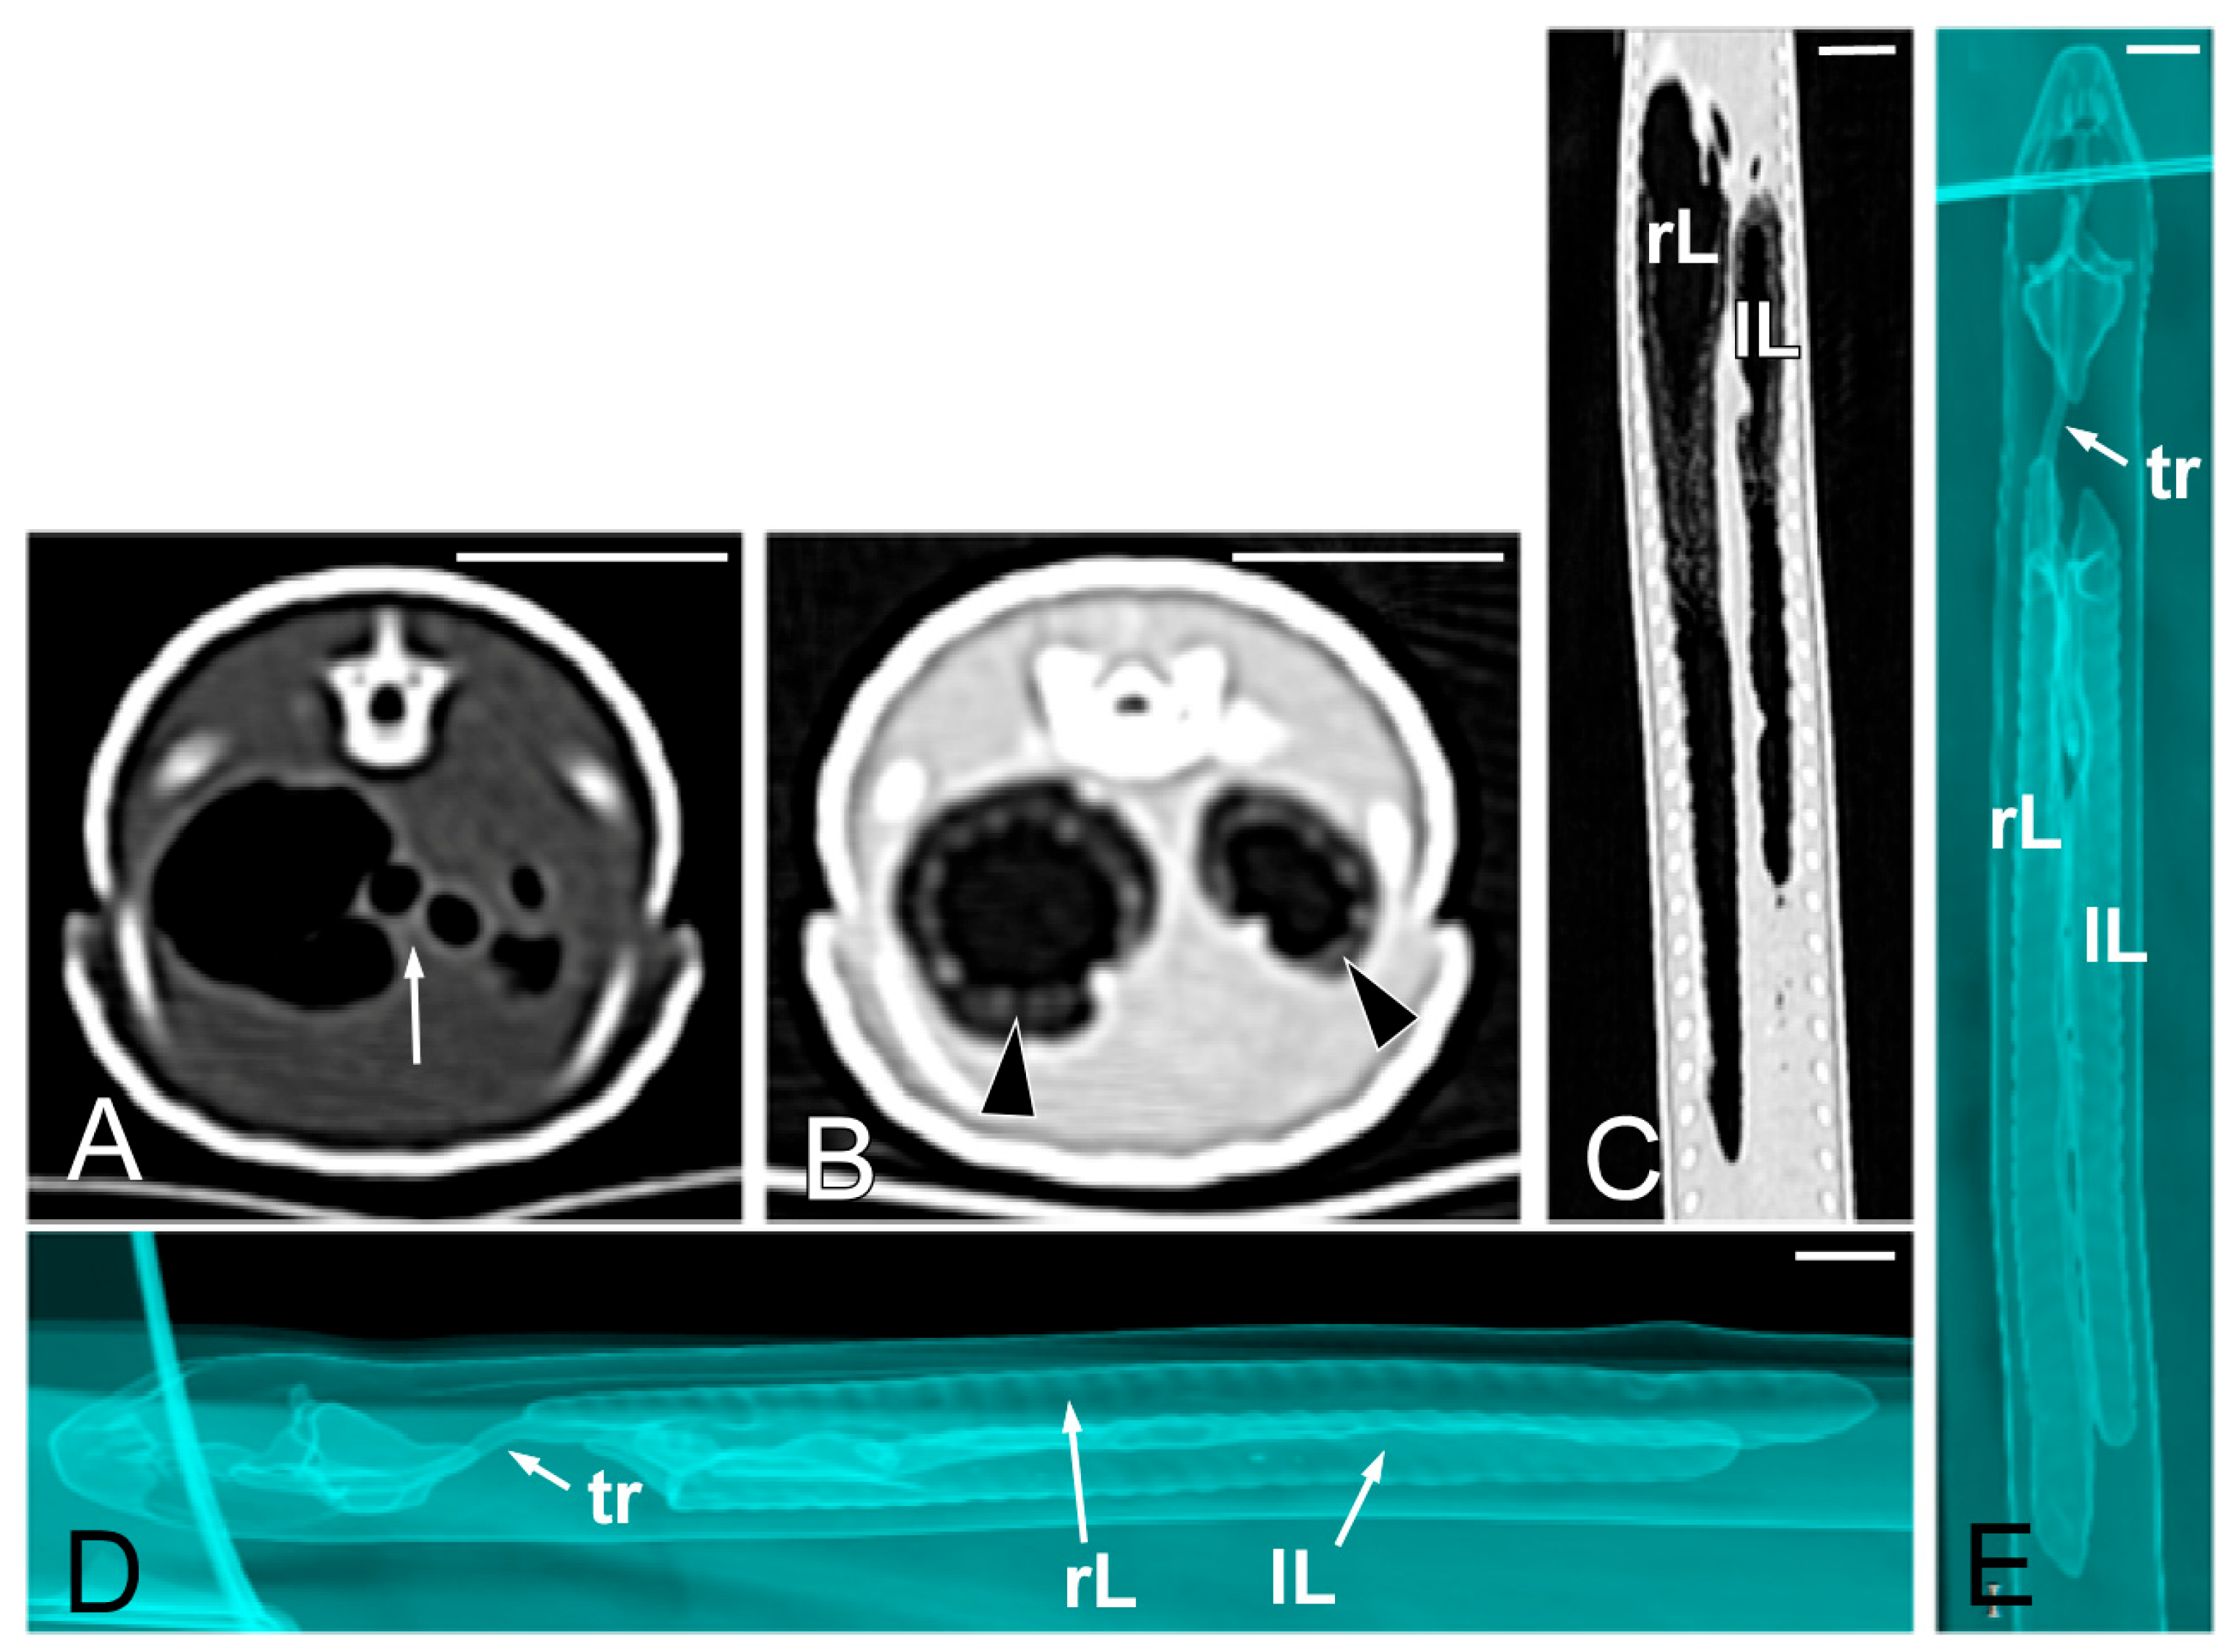

Concerning the CT images, the bifurcation of the trachea into the main bronchi was most clearly observed in the transverse plane (Figure 8A). The two lungs appeared as elongated structures with a reticular hypoattenuating area around an air-filled cavity. The distinction between the hypoattenuating area and just air was more distinctly identified in the transverse and dorsal planes using a postprocessing lung algorithm (Figure 8B,C). The 3D volume rendering using a postprocessing airways algorithm detailed the trachea and lungs (Figure 8D,E). Between the lungs, it was possible to identify those esophageal segments containing gas. On the contrary, those esophageal segments without intraluminal gas were indistinguishable from the surrounding soft tissues. The transverse and dorsal planes were the most useful for recognizing the esophagus (Figure 9). The liver appeared as an elongated organ with soft tissue attenuation located ventral to the caudal midsection of the lungs, on the right side of the stomach. Its margins were not well defined. The gall bladder was identified in the ventral part of the coelomic cavity as a hypoattenuating small oval structure surrounded by the hepatic parenchyma (Figure 10A). The differentiation between the gall bladder and the hepatic parenchyma was more evident in the postcontrast studies (Figure 10B–D). As in the case of the esophagus, the stomach and the small and large intestines were easily distinguished when containing intraluminal gas (Figure 11A) or hyperattenuating content (residual ingesta) (Figure 11B). The small and large intestines were located just caudal to the liver and the stomach, occupying approximately the caudal third of the coelomic cavity. The spleen and pancreas could not be identified when using CT.

Figure 11.

The CT images of Pseudopus apodus in the dorsal plane showing segments of the esophagus (white arrowheads), stomach (black arrowheads), and intestine (white arrows) with intraluminal gas (A) and with gas and hyperattenuating content (B). Bar = 10 mm.

Concerning the reptile digestive tract CT evaluation, some authors recommend the oral administration of contrast medium, as the gas-filled stomach is easy to see, yet the intestines are difficult to differentiate [27]. In our study, we performed the CT studies without oral contrast administration. We clearly identified those segments of the esophagus and intestine that had intraluminal gas or hyperattenuating content. However, there were other segments that showed a similar attenuation in comparison with other surrounding coelomic soft tissues. This fact made differentiating these esophageal and intestinal segments much more difficult. Instead, the stomach was easier to identify using the liver as a landmark, especially in postcontrast images. Valente et al. [29] reported the difficulty of distinguishing abdominal soft tissue structures, such as intestine portions, because of their small size and/or the lack of contrast between them and the surrounding tissues. In a study performed to evaluate the CT features of the coelomic cavity in green iguanas, black and white tegus, and bearded dragons [34], the stomach was well distinguished in the three species; individual small intestine loops were evident only in the green iguana, while the large intestine was particularly obvious in black and white tegus due to hyperattenuating content. In the study by Melero et al. [42], performed in chameleons, the esophagus and stomach were easy to identify, and intestinal loops were seen as tubular structures with a soft tissue attenuation wall and intraluminal small gas bubbles; however, in the same study the different intestinal segments could not be identified and only the colon could be distinguished with gas or feces when it was distended.